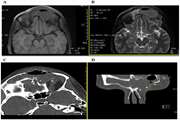

Surgical management of a giant glial hamartoma in a pediatric patient: a case report 1404/03/05 - 12:38